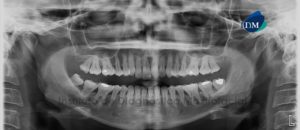

Paciente femenino de 19 años de edad, es referido al Instituto de Diagnóstico Maxilofacial – IDM (Sede Miraflores) para exámenes radiográficos para tratamiento ortodóntico y